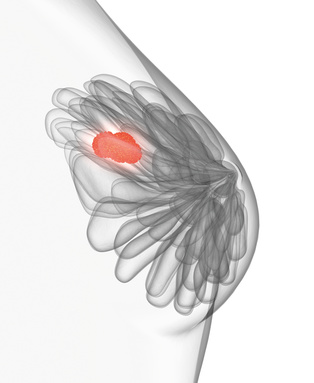

Was ist Brustkrebs?

Zunächst - den Brustkrebs gibt es nicht. Allgemein wird damit eine bösartige Wucherung bezeichnet, die aus dem Brustdrüsengewebe hervorgeht.

Zunächst - den Brustkrebs gibt es nicht. Allgemein wird damit eine bösartige Wucherung bezeichnet, die aus dem Brustdrüsengewebe hervorgeht.

Das Brustdrüsengewebe besteht aus den Drüsenläppchen und den Milchgängen (siehe Aufbau der weiblichen Brust). Je nach seiner Herkunft hat der Tumor unterschiedliche Eigenschaften und Verhaltensmerkmale. Generell verhalten sich Tumore, die von den Milchdrüsenläppchen ausgehen, gutartiger als jene, die von den Milchgängen herrühren.

Zur genauen Bewertung des Tumors sind jedoch noch viele weitere Merkmale - wie etwa die Hormonrezeptoren - zu berücksichtigen, weshalb das Tumorgewebe vor der Behandlung einer intensiven Analyse durch den Pathologen unterzogen wird. Jeder Brustkrebs ist individuell, weshalb eine Behandlung auch immer individuell auf die betroffene Frau abgestimmt wird.

Das wichtigste Merkmal ist die Ausbreitung des Tumors (TMN-Klassifikation), die eng mit der Größe bei seiner Entdeckung zusammenhängt. Je kleiner der Tumor bei seiner Diagnose ist, desto besser und erfolgreicher sind seine Behandlungsmöglichkeiten.